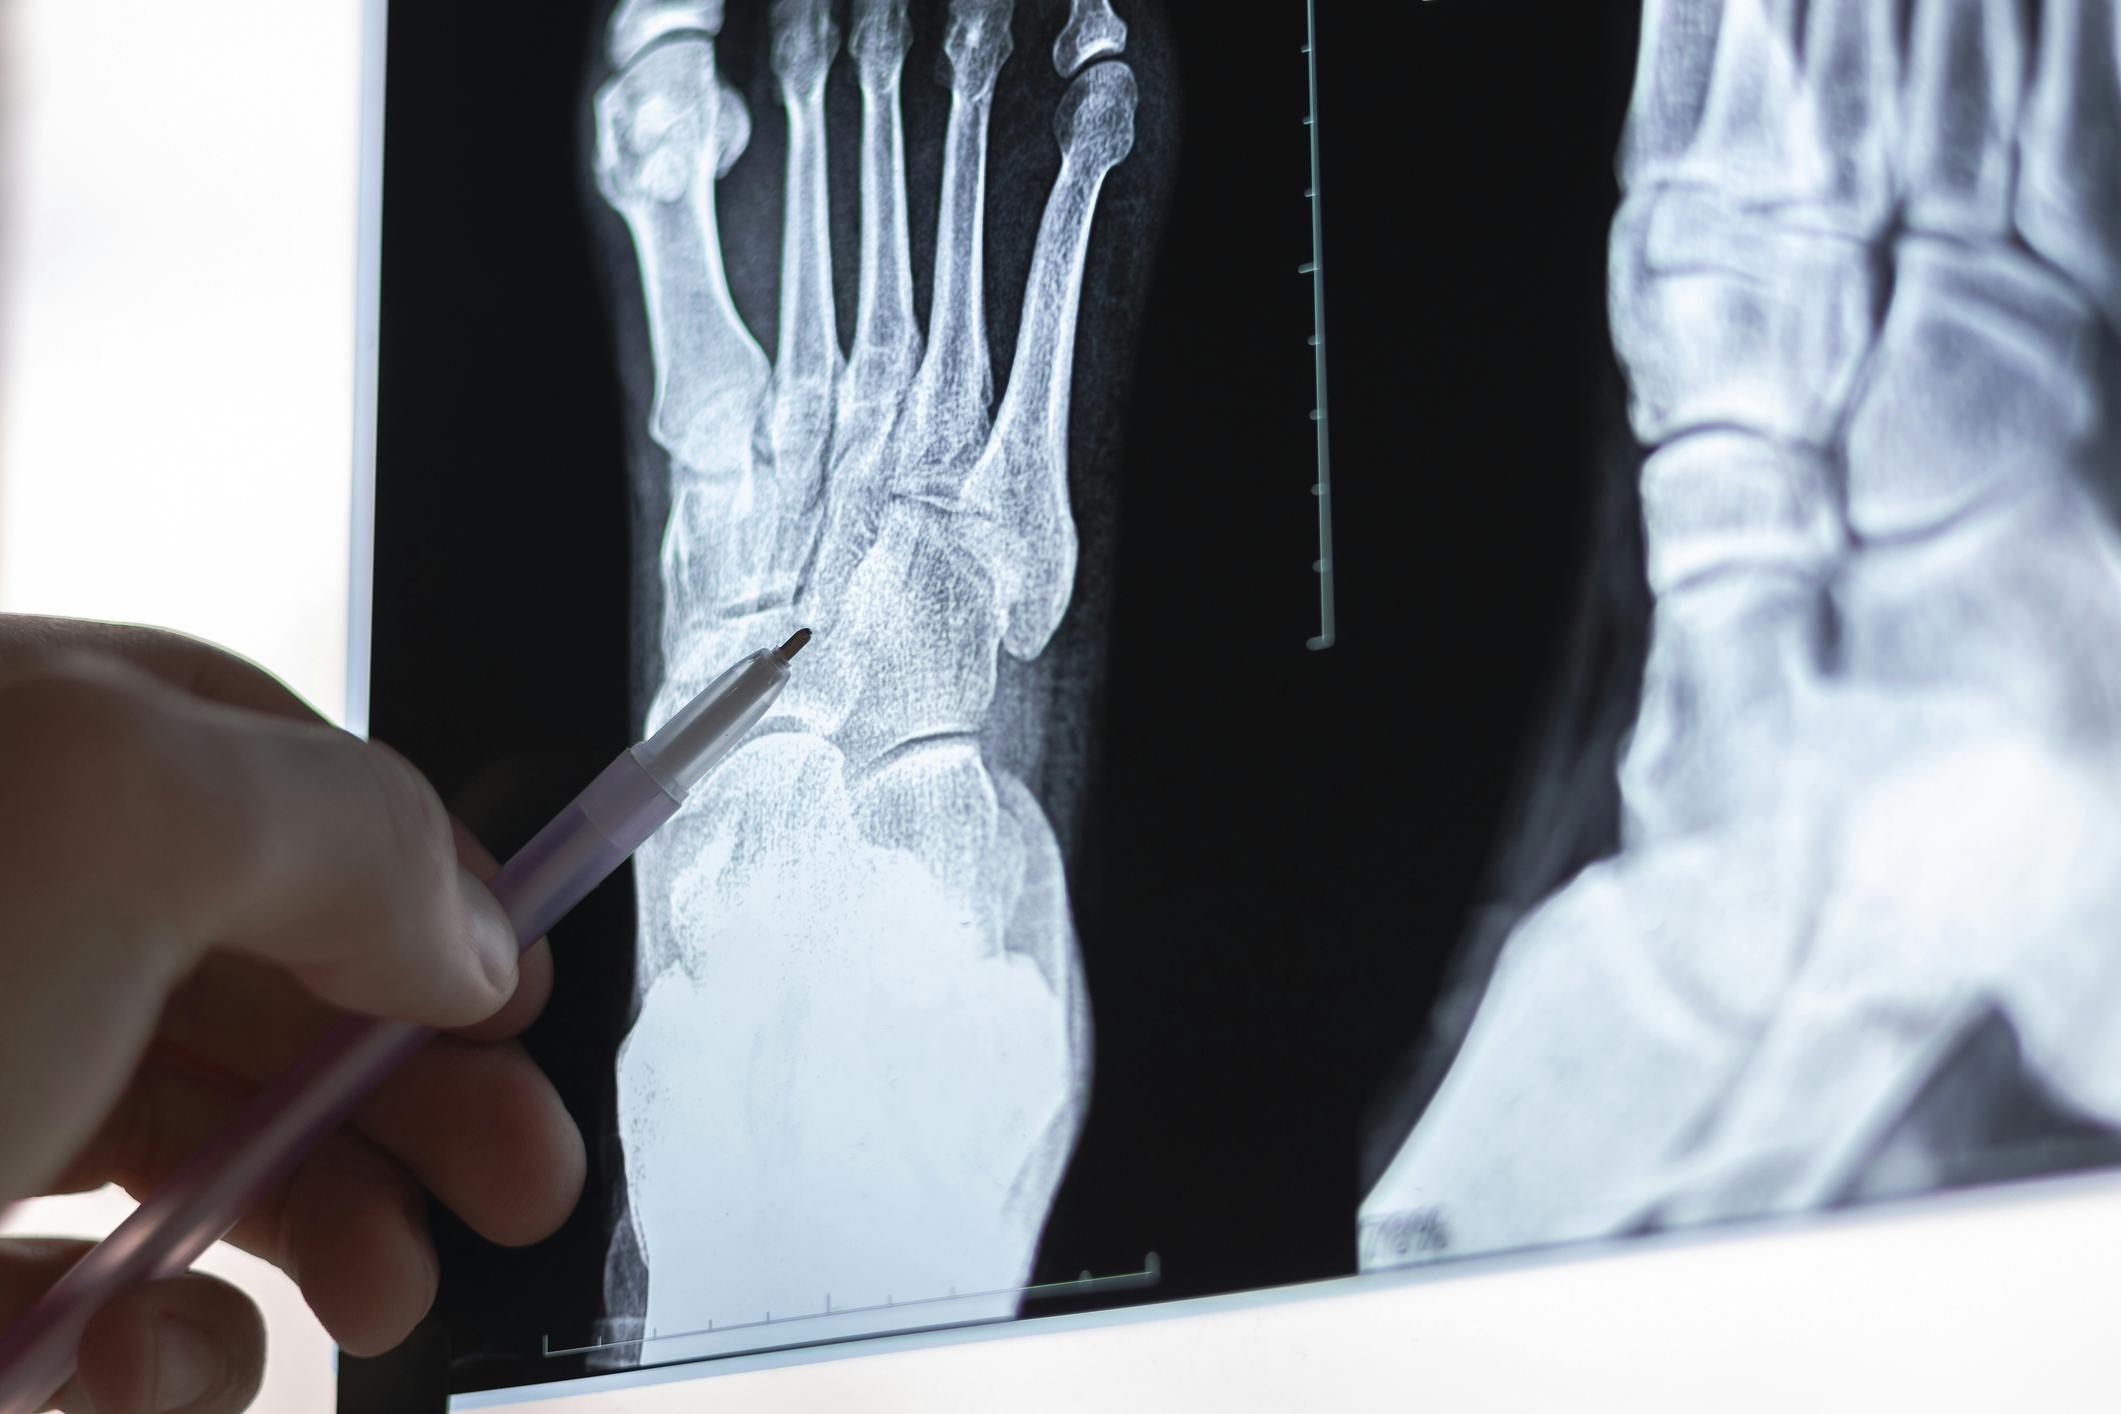

Foot and ankle fractures are common injuries caused by trauma, twisting, or impact. Premier Orthopaedic Associates offers expert diagnosis and treatment to promote healing, relieve pain, and restore full function to the injured limb.